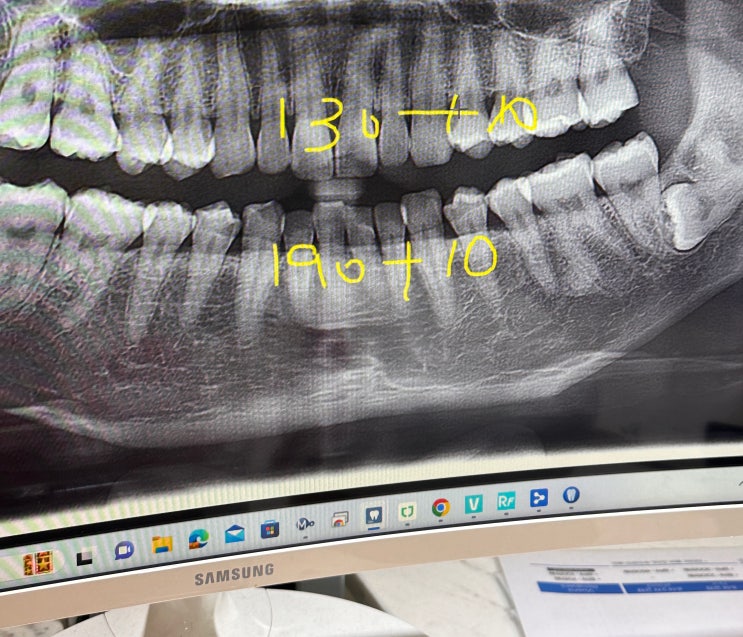

강남치과 앞니부분교정후기 4개월에 마치다 MTA교정기

강남치과 앞니부분교정후기 3개월차에 마치다 MTA교정기 앞니부분교정 2개월차부터는요? 앞니부분교정 2...

강남치과 앞니부분교정후기 한달차, 두달차 변화,MTA교정기

30대 중반이 되서야 알아본 앞니교정 강남에서 5군데 투어 후 마지막 상담했던 곳에서 앞니 위아래 부분교...

강남치과 앞니부분교정 상담투어 4곳 다녀온 후기

강남교정치과 상담투어 정리/강남으로 앞니부분교정 안녕하세요:) 벨라예요. 요즘 부쩍 아랫니 앞니가 좀 ...